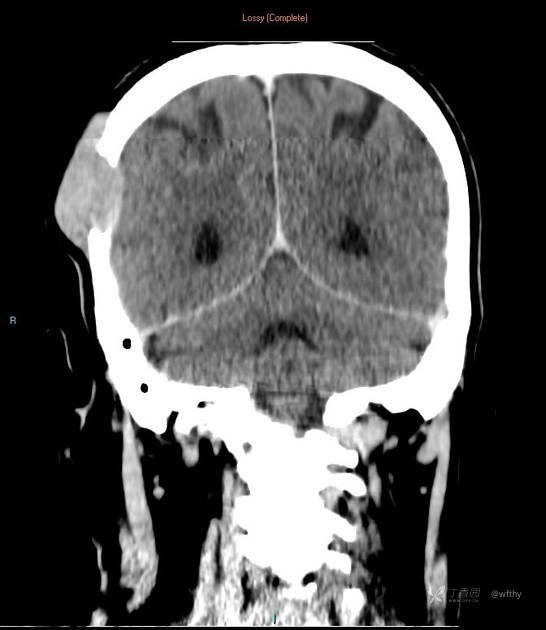

病例女65,头部肿块